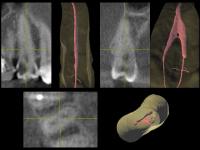

• Ниже (рис. 75-76) представлены фрагменты профильных срезов, наглядно показывающие зоны объединения (устьевая часть, апикальная треть) и расхождения (средняя треть, апекс) корневых каналов 1.5 зуба, а также пример подобной системы из Dental Anatomy & Interactive 3-D Tooth ATLAS (Brown and Herbranson).

| Рис. 75 Обтурация корневых каналов, данные томограммы и 3D диагностики |

Рис. 76 Пространственная иллюстрация эндо-системы (3-D Interactive Tooth ATLAS) |